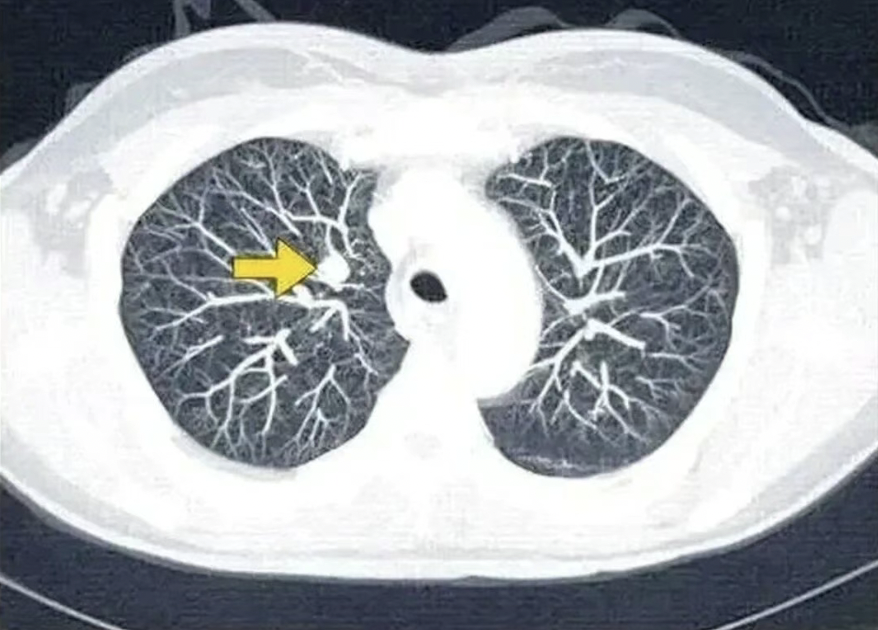

• 这4个症状出现2个,有可能是肺癌,建议尽快做个CT,查查肺

这4个症状出现2个,有可能是肺癌,建议尽快做个CT,查查肺

很多肺癌患者在确诊的时候就已经是晚期或中晚期了,早期的病人占比很少。其实,细究他们的患病历程,发现很多人在最开始都出现了一些异常症状,只是以为是“普通感冒”“累着了”“上火了”而忽视了。 当你的身体...【详情】